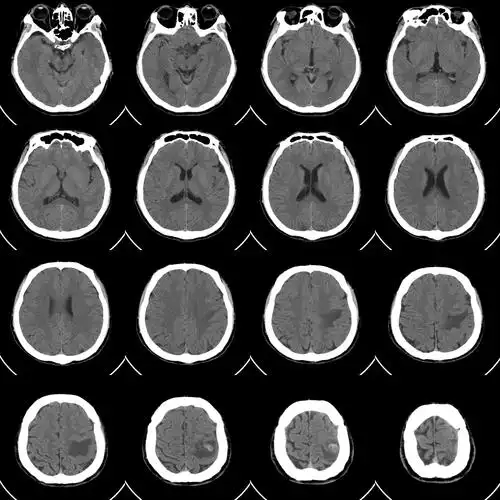

头ct平扫.jpg